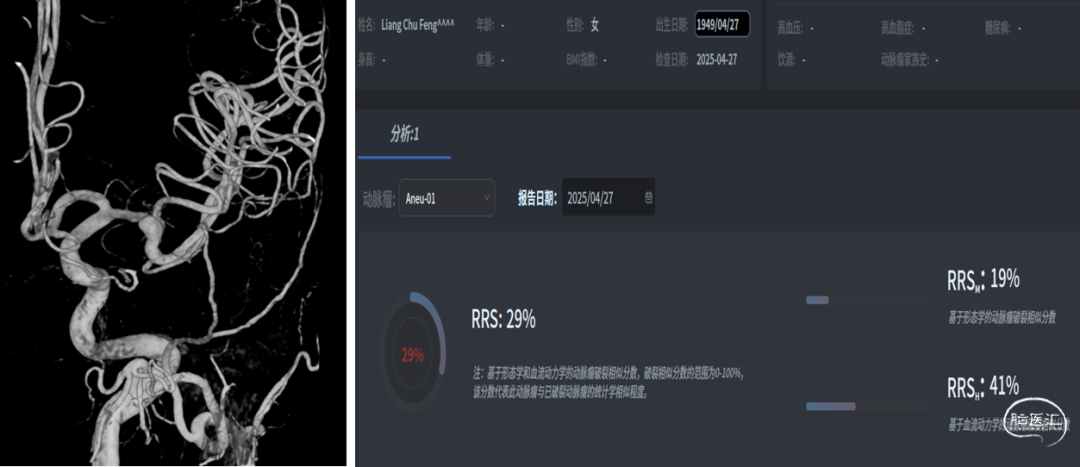

我院CTA

DSA

平均宽度(4.7+3.5)=4.1mm,最小深度3.4mm,选择SL6x2

CBCT